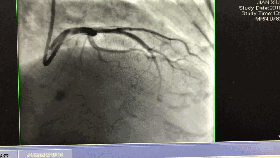

入院第5天行选择性冠脉造影+室间隔化学消融+ICD植入

◆左、右冠状动脉未见明显狭窄,前降支第一、第二间隔支消失,第三间隔支存在。

◆测压:左心室 235/12mmHg;左室流出道 162/27mmHg;主动脉108/57mmHg。

◆先植入单腔ICD,再消融第三间隔支。